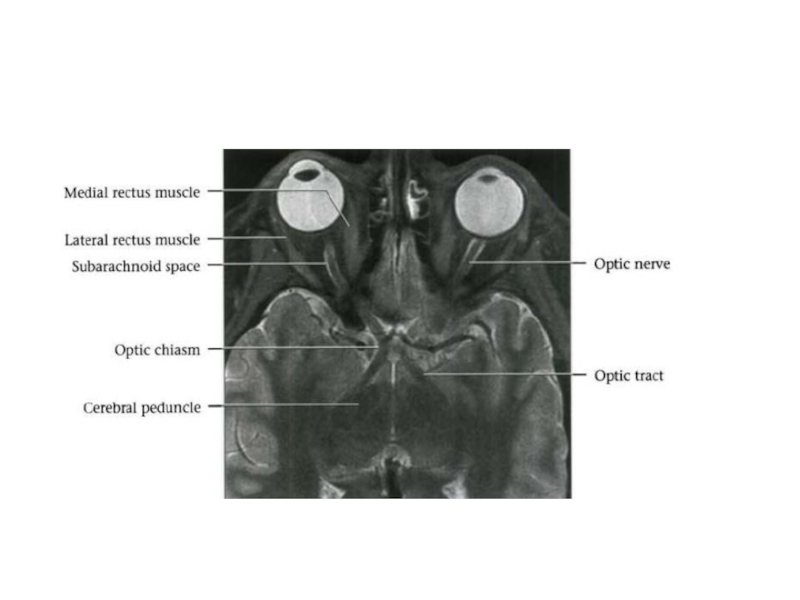

Слайд 5Зрительный нерв

Сетчатая оболочка (retina) – заложена цепочка из трех периферических

нейронов

1 нейрон - палочки (рецепторы черно-белого зрения) и колбочки (рецепторы цветного зрения)

2 нейрон - биполярные клетки

3 нейрон - ганглиозные клетки

Слайд 6Совокупность аксонов ганглиозных клеток образует зрительный нерв - зрительный перекрест (chiasma

opticum), в котором идут перекрещенные волокна от медиальных (носовых) половин сетчатки, волокна от латеральных (височных половин) идут со своей стороны- зрительный тракт (правый зрительный тракт – волокна от правых половин сетчатки, левый зрительный тракт – волокна от левых половин сетчатки)

4 нейрон – располагается в латеральном коленчатом теле и подушке таламуса

Латеральное коленчатое тело – первичный зрительный центр

Аксоны 4 нейрона образуют зрительную лучистость (пучок Грасиоле) в коре затылочной доли

Корковая зона зрения – верхний (принадлежит клину) и нижний край (принадлежит язычной извилине) шпорной борозды (sul.calcarinus) на медиальной поверхности затылочной доли